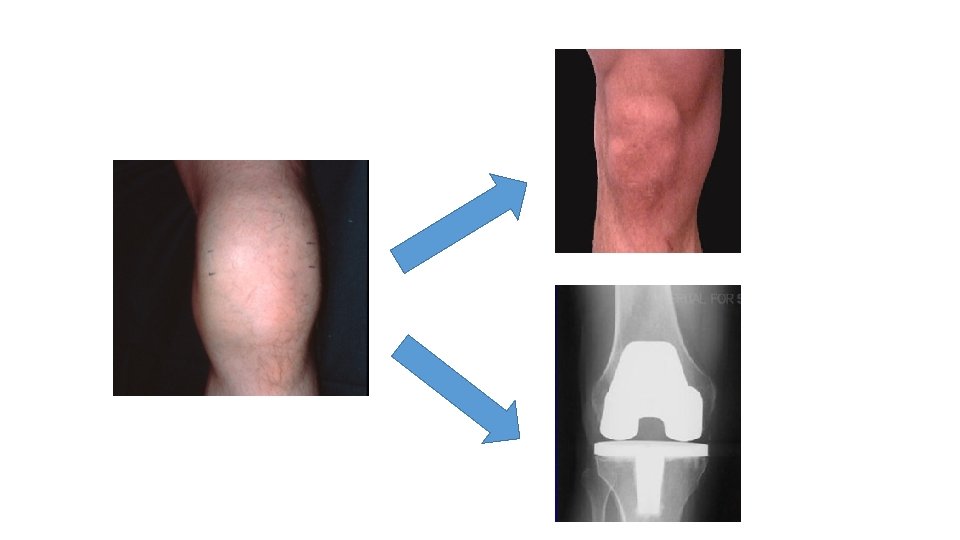

Joint bleeds MRI evidence of joint damage

No joint bleeds No MRI damage

Joint bleeds No MRI damage

NO Joint bleeds BUT MRI damage

• Subclinical joint bleeding? • Management? • Optimise prophylaxis?

• Subclinical joint bleeding? • Management? • Optimise prophylaxis? Could we identify susceptible individuals?